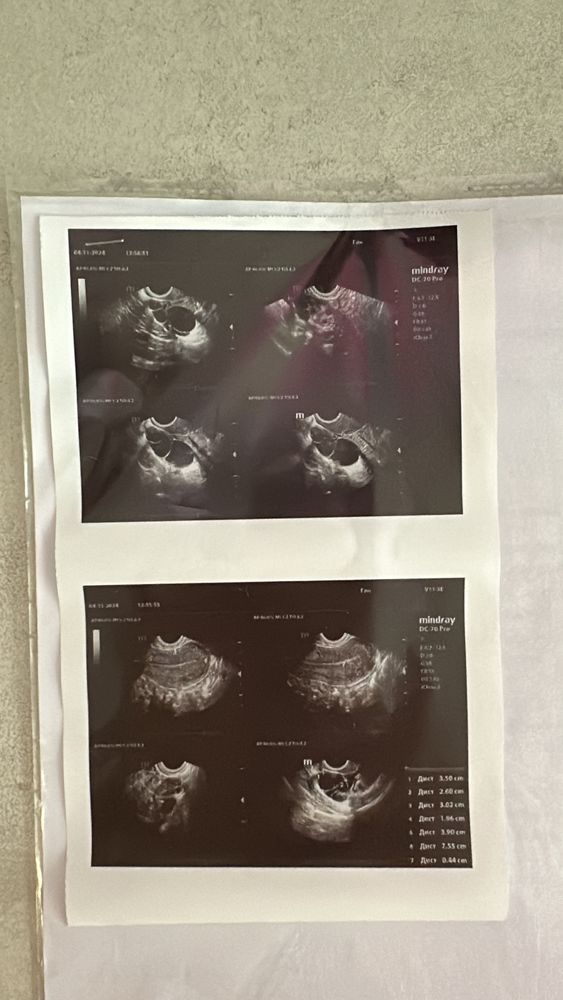

Гидросальпигс?

Ох…неужели это все происходит со мной? Предстоит лапара, врач не может сказать что это. То ли параовариальная киста то ли это труба с жидкостью…страшно до ужаса. Что вообще останусь без труб. На узи со второй трубой все хорошо. Беременность в августе хоть и выкидыш случилась как раз справа.